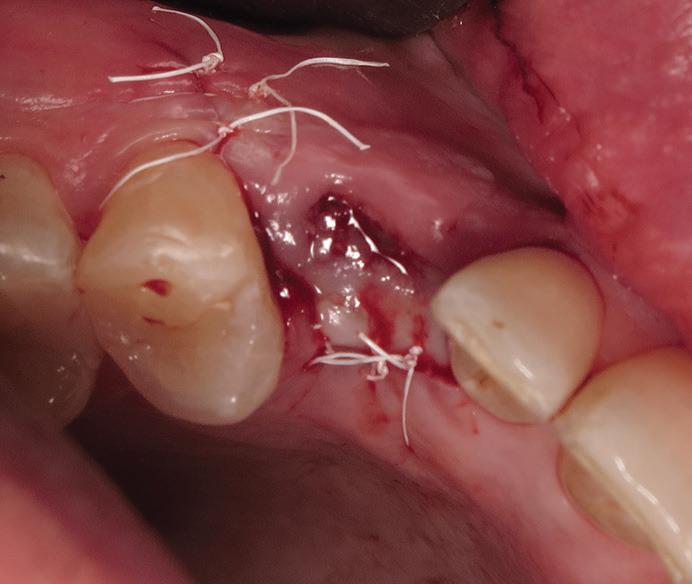

After antiseptic procedures, the surgical site is evaluated. In Fig 4, the site shows good hard and soft tissue volume consistent with that seen in the preoperative planning scans.

Fig 5. The reflected flap reveals bleeding vital bone and maintenance of ridge width.

Fig 4. The fully healed site is ready for implant placement.

Fig 8. The implant site is closed with PTFE sutures in a 2-stage approach.